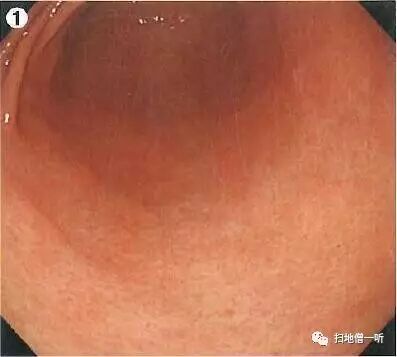

A:胃癌在图2。HP未感染胃癌。

整体胃粘膜光滑,未见明确萎缩。白光下可见无数小红点规则排列(RAC),所见为HP未感染征像。